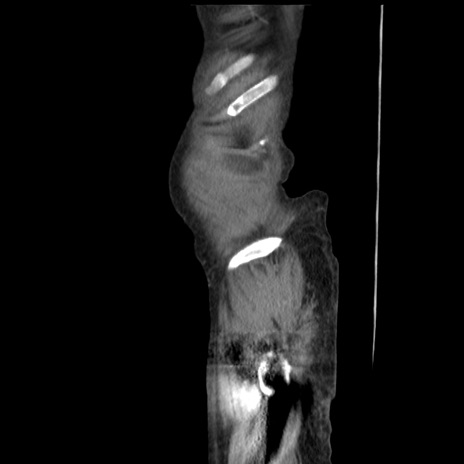

症例31(矢状断像)

【症例】80歳代 女性

【主訴】腹部膨満感

【現病歴】他院にて肝硬変にてフォロー中。1週間前から便秘、腹部膨満感、臍部腫瘤あり受診となる。

【既往歴】肝硬変

【身体所見】腹部膨隆あり、皮膚変化なし、疼痛なし。

【データ】WBC 4600、CRP 0.25